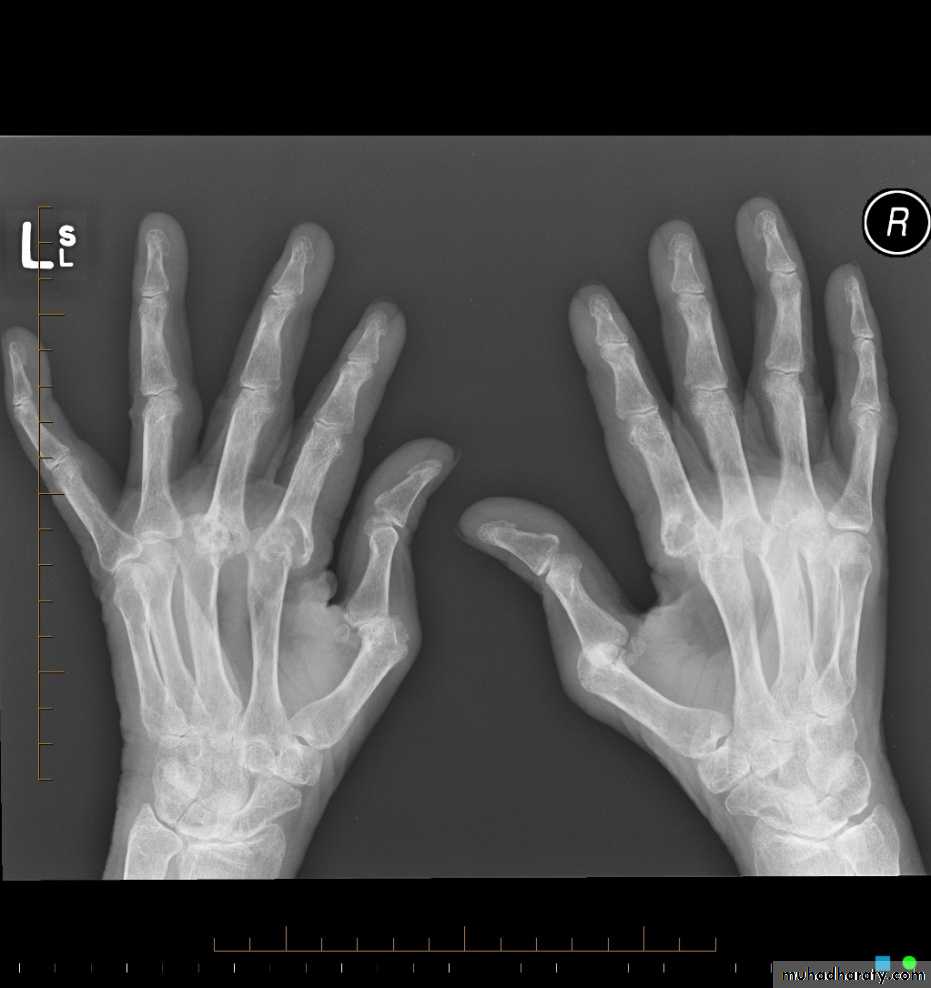

Rheumatoid arthritis.

(A) The initial radiograph shows a hint of early trabecular loss around the proximal interphalangeal joint of a finger with preservation of the joint space and early marginal cortical loss at thebase of the middle phalanx.

(B) The subsequent radiograph shows established erosive change in the area of ill-defined demineralisation in association with joint space narrowing .

Gross rheumatoid arthritis at the carpus with ulnar deviation,

subluxation and joint narrowing at the metacarpophalangeal joints.Boutonniere deformities are present at the index and little fingers.

• Rheumatoid arthritis. Bilateral changes are fairly symmetrical. Soft-tissue swelling is demonstrated, especially over the ulnar styloids. Erosions are demonstrated at the carpus, distal radius and ulna, with joint space narrowing and collapse of bone. Metacarpophalangeal erosions are also seen associated with joint space narrowing. There is a swan-neck deformity of the right fifth distal interphalangeal joint